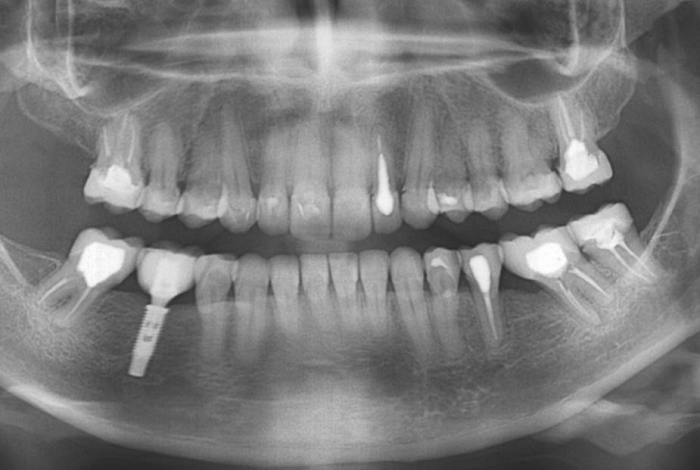

Imagem inicial

Raio X inicial apresentando ausência do molar inferior direito